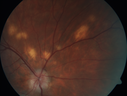

31 year old man with vision loss in the right eye more than the left eye. He has an anaplastic astrocytoma diagnosed 10/2017 the first one was 10/2014. These are different locations. They are treating them with Chemotherapy and Avastin. It might be that one might have spread from the other. He was clean for 3 years. He is on Avastin and Temozolomide but his blood counts have been good. December 2017 he had a herpes superficial infection in the right eye which responded to treatment. The last neurosurgery was October 2017. Going to Duke June 5 and seeing a neuroophthalmologist there. VA OD: Dcc20/40 PH20/25 NccJ5 VA OS: Dcc20/16 PH20/10 NccJ1+ His fundus is presumably nocardia, pneumocystis, aspergillis or cryptococcus. His LP was negative and he was tried on a course of antifungals. He was then lost to followup

Multifocal Choroiditis - Pneumocystis - aspergillis - cryptococcus730 views31 year old male with anaplastic astrocytoma on chemotherapy with mild vision loss in the right eye. LP did not reveal organism. He was placed on a trial of anti-fungal medications and lost to follow-up00000